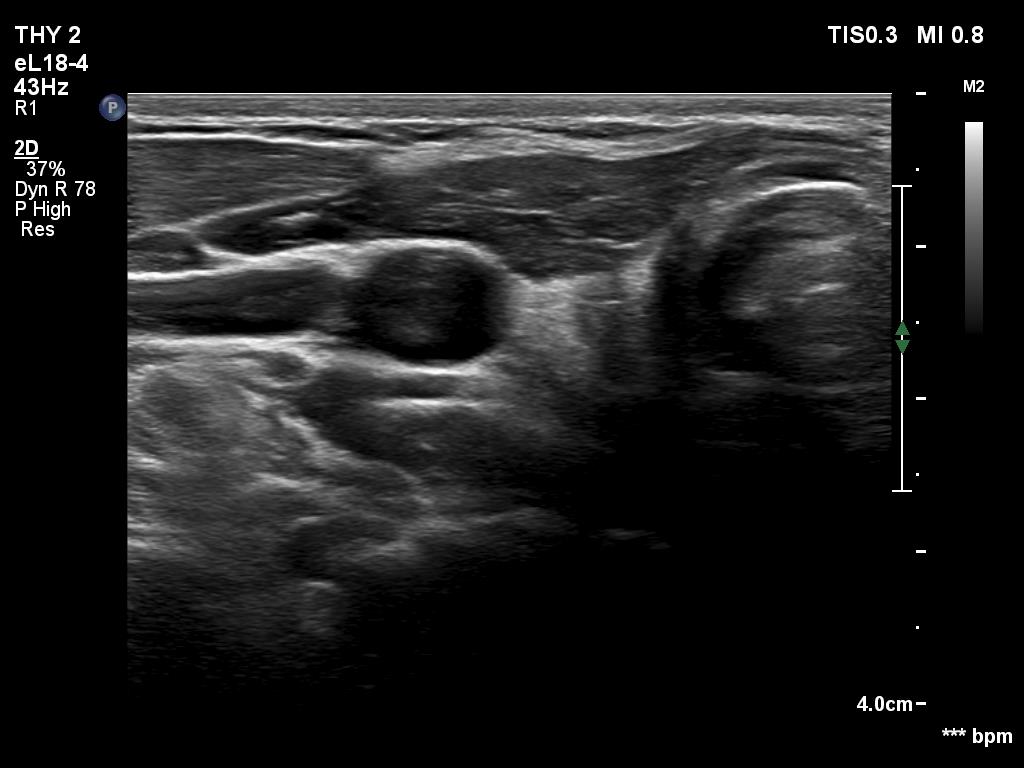

First examination (1st to third rows of images):

Clinical data: A 14-year-old boy was referred for evaluation of a nodule discovered by himself.

Palpation: a hard, not freely moveable nodule in the isthmic part of the left lobe.

Hormonal examination: indicated euthyroidism with TSH 2.09 mIU/L.

Ultrasonography revealed a hypoechogenic nodule in the ventromedial part of the left lobe. The nodule had irregular borders, contained microcalcifications and displayed perinodular and irregular intranodular blood flow.

Cytology: follicular tumor.

Based on the ultrasound and cytological pattern combined, the probability of cancer was greater than the average.